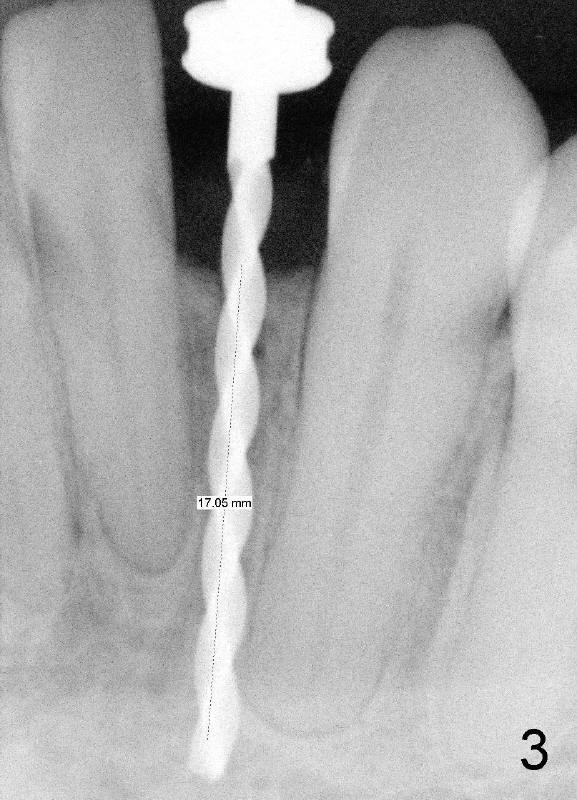

A 44-year-old black lady with ortho several years ago requests fixed restoration for #23 with narrow mesiodistal width (Fig.1). Treatment options are proposed: fixed prosthetic denture and implant. After discussion of advantages and disadvantages of each option, the patient agrees to have implant restoration. A 1.5 mm pilot drill is used to create osteotomy (Fig.2,3). After using 2.0 mm and 3.0 mm tapered osteotomes through the cortex at the crest, 3x17 mm 1-piece implant is placed (Fig.4) and temporary crown is immediately cemented with no centric or lateral occlusion. The patient is doing fine postop, although there is very mild percussion involving the tooth #24, three days postop. Fig.5 and 6 show that the temporary crown is bonded to the neighboring teeth interproximally and lingually. Retrospectively, ortho should have been done to torque the root of the tooth #22 prior to implant placement. Fig.3,4 show that there is space between #21 and 22.